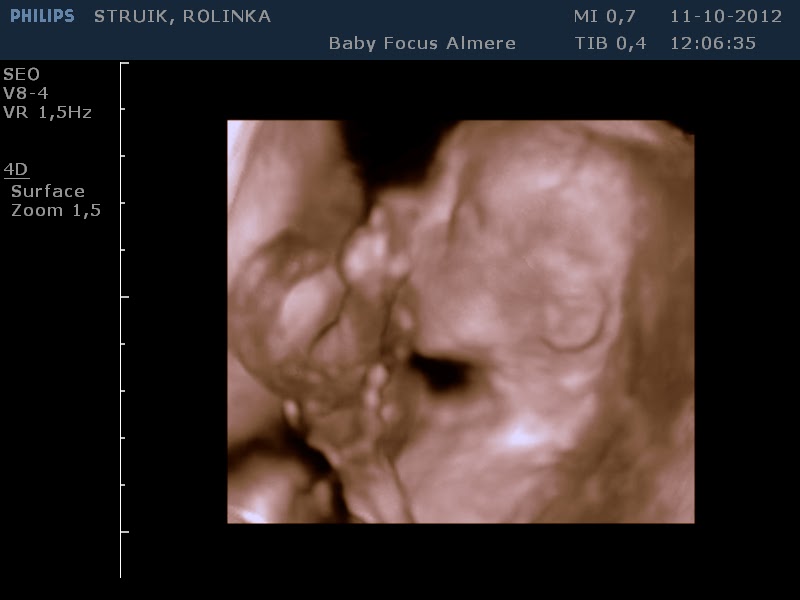

Vanmorgen was het weer DUBBELOP genieten. Ik kreeg van M dit jaar mijn verjaardagscadeau vervroegd. Een 3 en 4D echo bij

BabyFocus in Almere.

Verschil tussen 3 en 4D is, dat de eerste stilstaande beelden zijn, de

andere bewegende. Onze tweeling op deze manier bekijken was voor ons

De tweeling was wakker en super actief. Er werd druk

tegen de doppler getrappeld en ze draaiden om en om! Soms kwamen de

billen zo hoog dat we het aan de buitenkant konden zien! Ze waren ook

erg relaxed en lagen zo nu en dan knus tegen elkaar. Lekker met de

knuistjes in hun gezicht, opgerold tot een balletje. Net twee egeltjes

klaar voor hun winterslaapje. Wat een genot om je kinderen op deze

manier te kunnen bekijken al voor ze er zijn! Helemaal compleet... we

hebben vingertjes en teentjes geteld, zelfs de oogwimpertjes konden we

zien! We hebben een hele serie prachtige foto´s van de jongens

meegekregen en de hele echo op DVD in bewegend beeld! Een mooie

herinnering aan een nog mooiere ervaring...